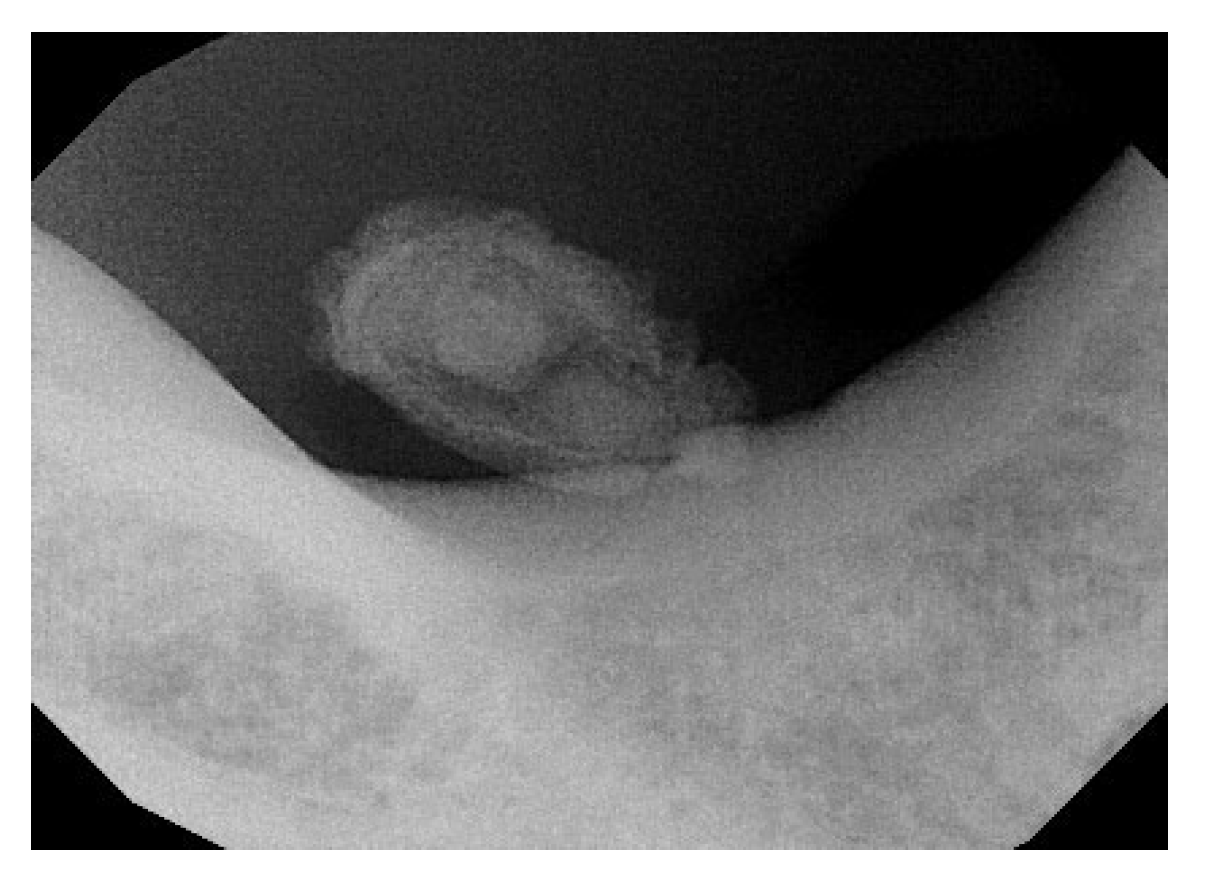

| Barak et al. (1993) [20] | Case series | 6 cases, 2M (22-54 Y) 4W (19-32 Y) |

Wharton’s duct: 4 patients. Submandibular gland: 2 patients. |

Co2 laser | 10W in continuous mode | - | No complication. Postoperative Swelling in 2 patients (Hilus of submandibular gland) | 1 year. | Complete healing in 7 to 20 days |

| Yang et al. (2011) [21] | Case series | 19 cases, 12M, 7FW (8- 54 Y) |

In the posterior half of Wharton’s duct. | Co2 laser | 4-6W in continuous mode | - | One patient developed ranula formation after laser surgery | 1-3,5 years. | The results suggest that transoral CO2 laser sialolithectomy is a simple, safe, and low-complication procedure suitable for outpatient treatment. |